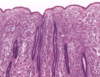

Uterus - endometrium, myometrium, lamina propria, endometrial epithelial glands

Endometrium - endometrial epithelial glands (simple columnar epithelium)

Stratum functionale of endometrium, stratum basale of endometrium, myometrium